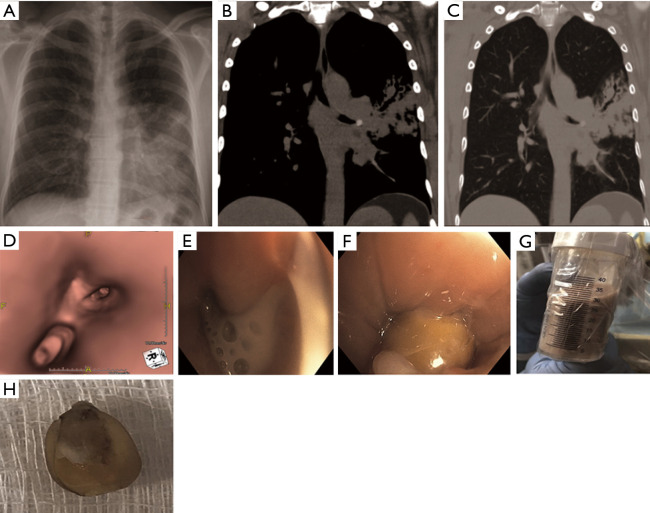

Figure 1.

A 46-year old man, never smoker, with history of Asthma presented with non-resolving cough and hemoptysis. He received two prior antibiotic treatments for presumed pneumonia a month apart with mild improvement. Chest imaging revealed findings concerning for necrotizing pneumonia as result of lingular obstruction (A-C). Computed tomography scans revealed high density foreign body (B) and post obstructive bronchiectasis (C). 3-dimensional reconstruction of the tracheobronchial tree was performed to localize the obstruction (D). After receiving intravenous antibiotics for 72 hours, patient was intubated electively given concern for “spill-over” of pus from relief of obstruction. A significant amount of pus was suctioned post-extraction of the foreign body (E-G). Foreign body was determined to be a corn kernel (H). Patient completed a course of antibiotics and had no symptoms on a follow up visit.